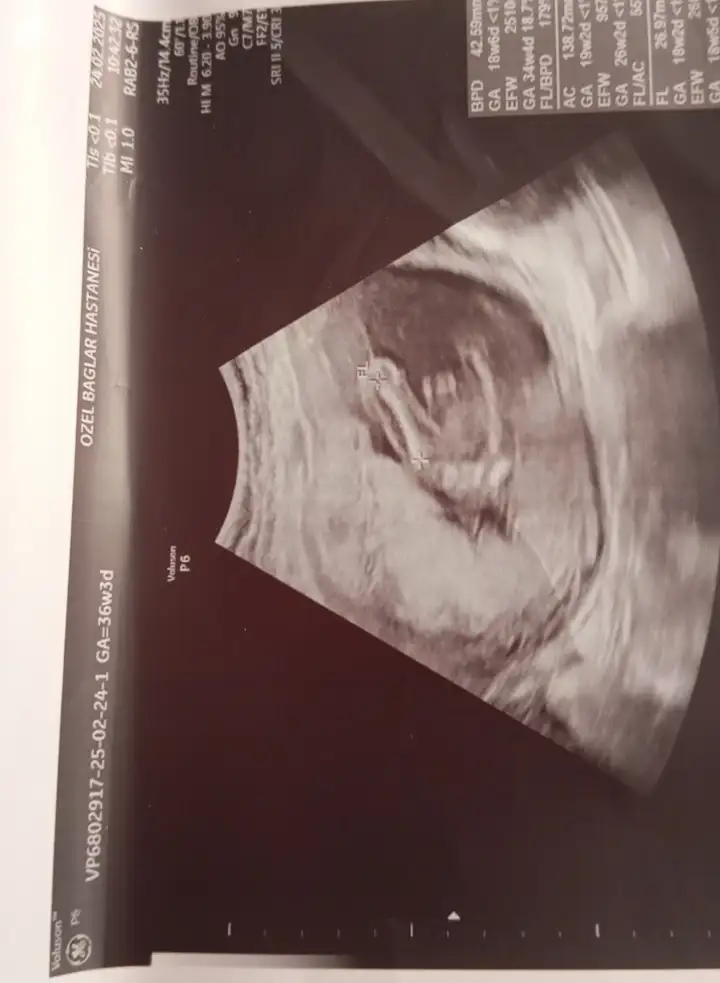

Kızlar sizce nuba göre cinsiyet nedir 12+5